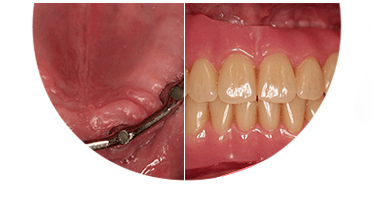

Plano de tratamento: Colocação de 4 implantes superiores e 2 implantes inferiores. Confeção de uma barra superior e colocação de 2 locators® na parte inferior. Confeção de uma prótese superior e outra inferior removível, com encaixes na barra e locators®.

A escolha deste plano de tratamento deve-se ao facto de o paciente querer uma solução total, mas não completamente fixa, uma vez que não tinha muita destreza manual para higienizar uma prótese fixa. Desta forma, conseguiu uma solução bastante retentiva (devido aos encaixes) mas que consegue remover para uma higienização correta.